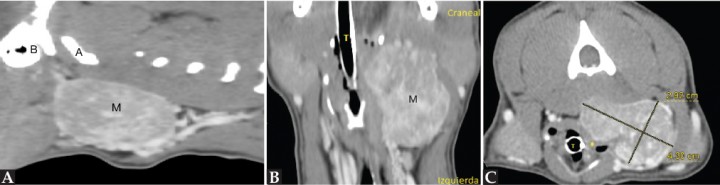

En la TC se identifica la presencia de una masa cervical izquierda (3 cm de alto x 4 cm de ancho x 5,3 cm de largo), originada en el área de la carótida común izquierda y vena yugular interna a la altura de C3-C4 (Figs. 1 y 2A). Las tiroides resultan dentro de la normalidad. En el estudio poscontraste la masa realza de manera marcada y heterogénea. En su extensión dorsolateral, la masa se extiende hacia la porción dorsal, sobre todo izquierda, de laringofaringe y esófago craneal, causando efecto masa desplazando a la derecha la laringe y aparato hioideo, y ventrolateralmente a la derecha el esófago craneal (Figs. 2B y C). También desplaza dorsolateralmente a la izquierda la musculatura cervical hipoaxial, y la porción más rostral en el lado izquierdo se extiende dorsalmente hacia la base del cráneo, pero no se detecta infiltración intracraneal ni signos de lisis ósea en la base del cráneo (Fig. 3). Aunque la masa parezca bastante bien definida no se puede descartar una afectación de la laringe/laringofaringe y de la musculatura cervical. Se visualiza también una congestión venosa y arterial regional (arteria carótida común y vena yugular interna izquierdas) secundarias a la masa, y aunque no se detectan signos de trombosis u oclusión, no se puede descartar una invasión vascular de estos vasos que están envueltos por la masa.

<p>Imágenes de TC poscontraste en ventana de tejido blando de la masa cervical izquierda. (<strong>A</strong>) Plano sagital. (<strong>B</strong>) Plano dorsal. (<strong>C</strong>) Plano transversal. Nótese el desplazamiento de la laringe (*). M: masa; A: atlas; B: bulla timpánica izquierda.</p>

Figura 2

Imágenes de TC poscontraste en ventana de tejido blando de la masa cervical izquierda. (A) Plano sagital. (B) Plano dorsal. (C) Plano transversal. Nótese el desplazamiento de la laringe (*). M: masa; A: atlas; B: bulla timpánica izquierda.